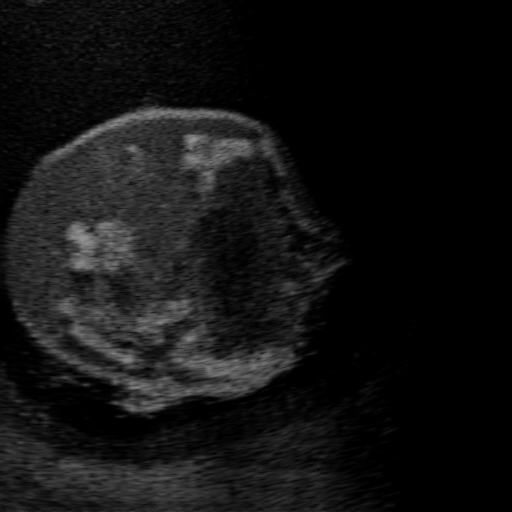

Qualitative Results. Fig. 3 shows a visual comparison of the three model variants on four examples. The baseline L2HM fails to preserve anatomical structures due to missing structural information in the input images. Resulting ambiguities in the network prediction cause artifacts such as blur in regions that feature fine details such as bones. Providing segmentation maps as additional input (L2HMS) greatly reduces such artifacts as shown in Fig. 3(c). However, L2HMS still struggles in modeling complex non-local features such as directional occlusion artifacts, note the lack of acoustic shadows in Fig. 3(c). In contrast, our final model L2HMSA is able to accurately synthesize these features and produces translations significantly closer to the target, as demonstrated in Fig. 3(d). In particular, our proposed model with segmentation and attenuation integral maps is able to recover both missing anatomical structures and directional artefacts.

(a) Input

(b) L2HM

(c) L2HMS

(d) L2HMSA

(e) Target